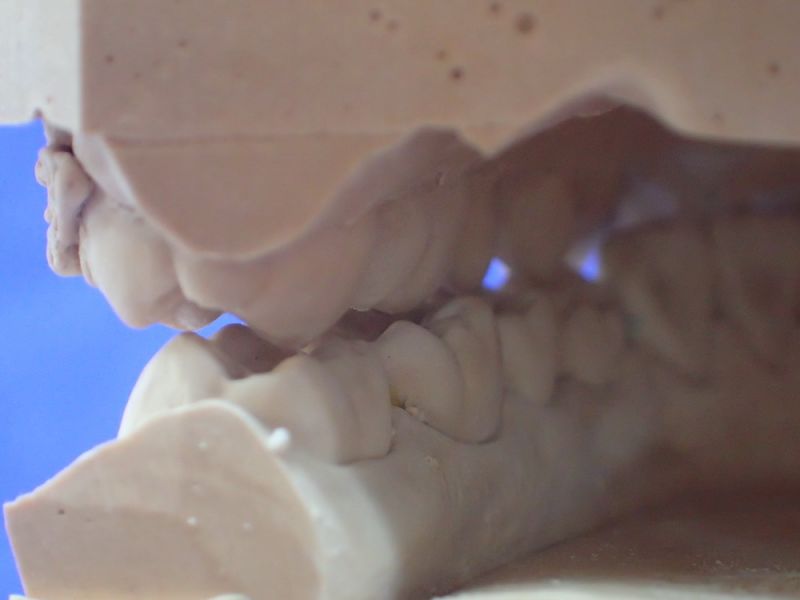

Es erfolgt dieErstuntersuchung und die Herstellung und Eingliederung eines adjustierten Aufbissbehelfs zum Nachweis einer CMD.